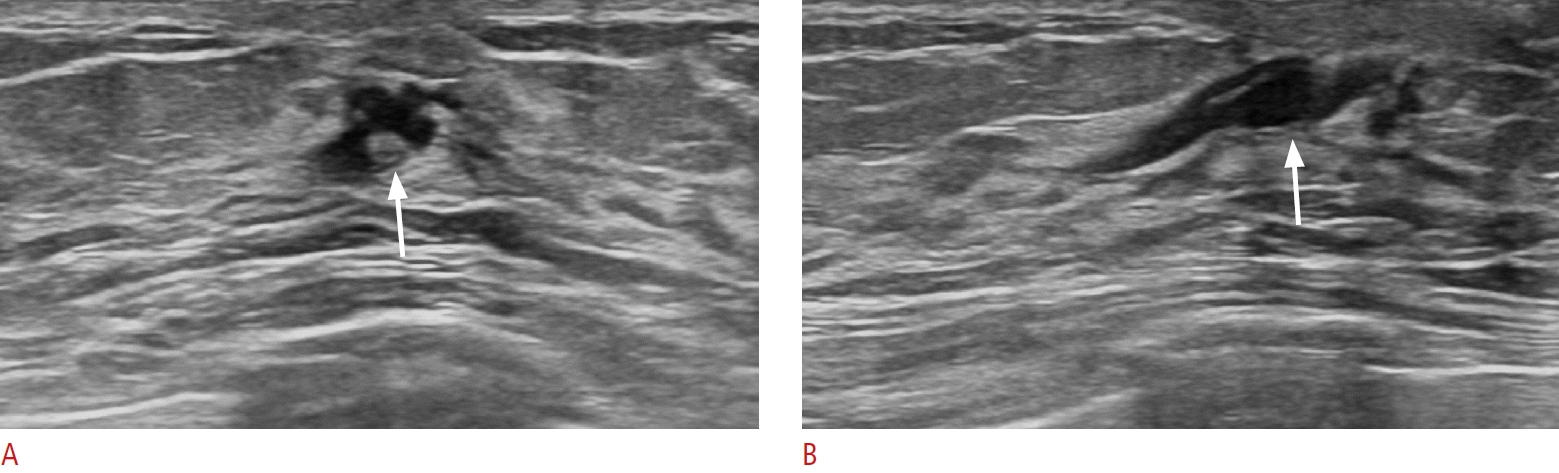

47. Boonjunwetvat D, Rengganis AA, Manasnayakorn S, Vongsaisuwon M, Tantidolthanes W, Sampatanukul P. Sonographic focally thick duct of breast found in screening, why is it concerning? A report of three cases. Breast Dis. 2022; 41:215–219.